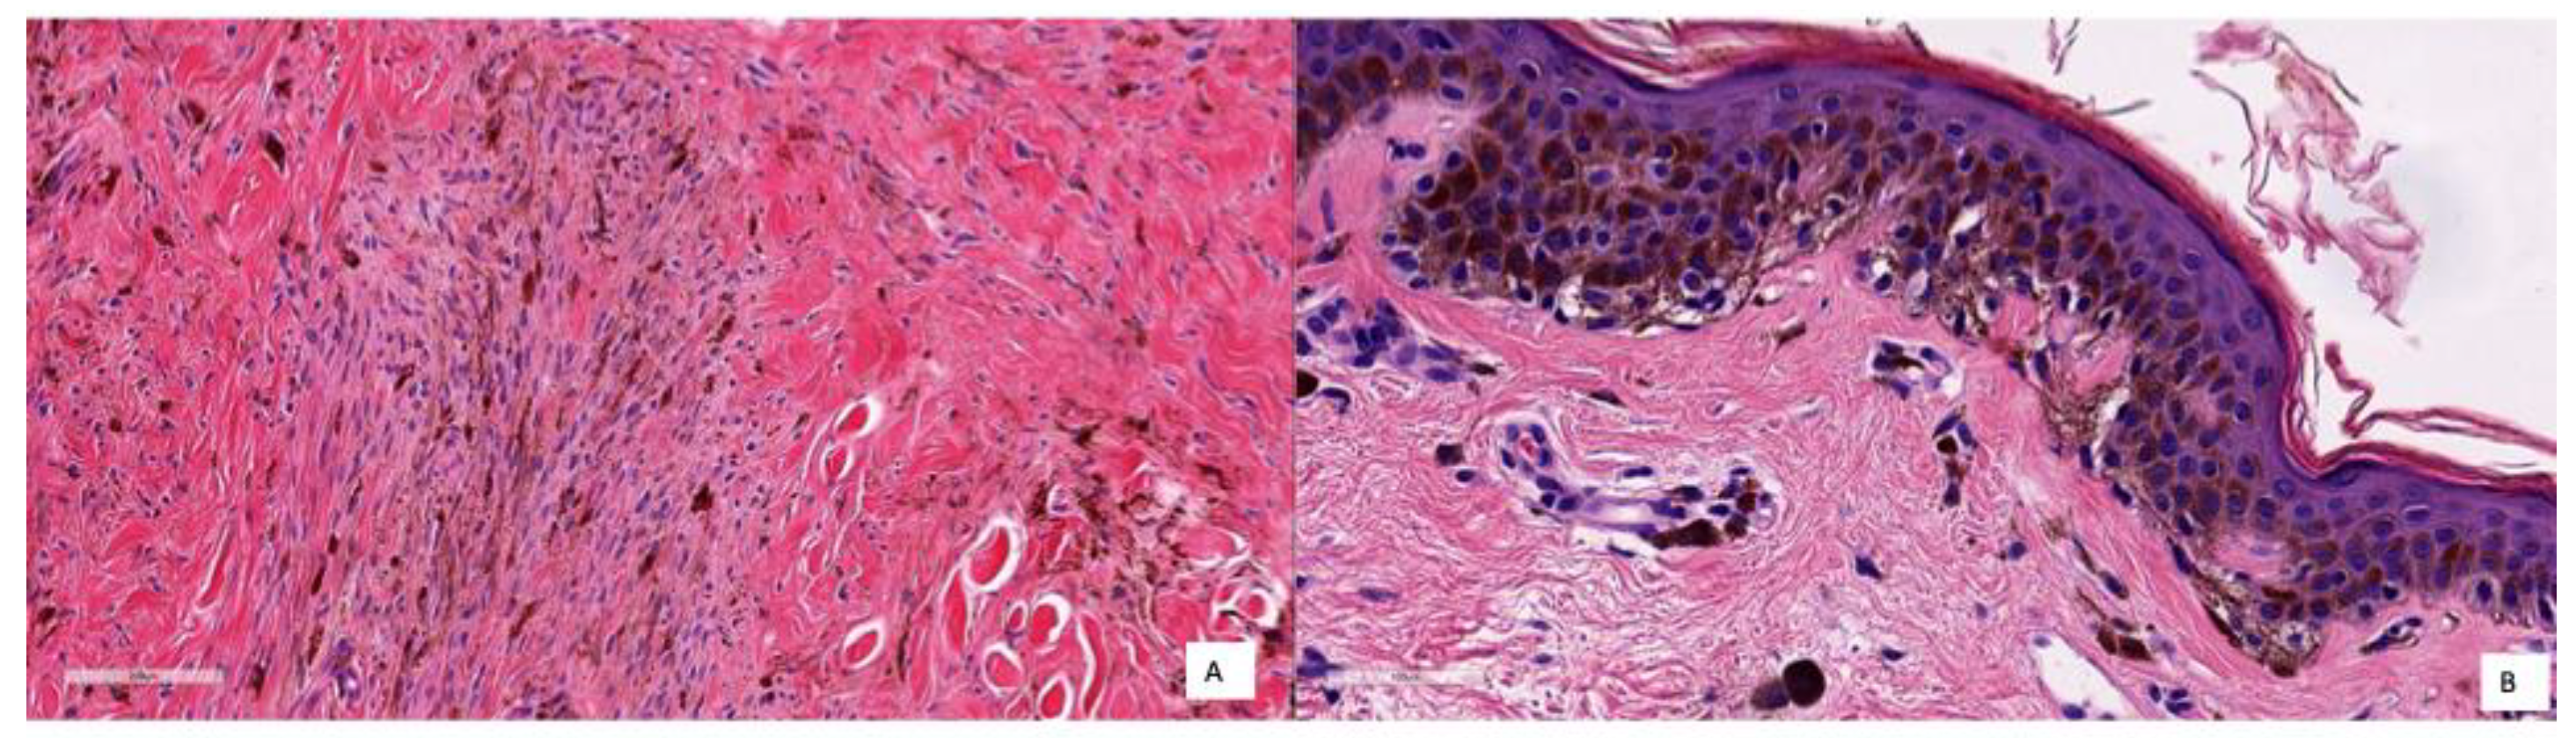

To better illustrate how the model diagnoses, different pictures of the cases corresponding respectively to TNs, TPs and FPs are shown in Figure 8, Figure 9 and Figure 10. Figure 8 shows several examples of TN cases, including a case of dermal melanocytic nevus (Figure 8A), a Reed nevus (Figure 8B), a Spitz nevus (Figure 8C) and a dysplastic nevus (Figure 8D). Figure 9 shows two examples of True Positive (TP) cases, including a spreading superficial melanoma of 3.79mm of Breslow thickness with balloon degeneration (case A) and a superficial spreading melanoma, ulcerated of 5.5 mm of Breslow thickness (case B).

Figure 10.

Representative FP cases: (A) deep cellular blue nevus, characterised by dermal proliferation of spindle, fusiform, or ovoid cells with associated melanin pigment (present both within melanocytic tumour cells and macrophages), and stromal sclerosis; (B) lentiginous nevus, exhibiting basal melanocytic proliferation of pigmented melanocytes.

As said earlier, only two cases were classified as FP with the KNN model and only one with the RF model. Coincidentally, both models failed to classify the same case (a deep blue nevus) as benign. The histopathological features of the two FP cases are compiled in Table 5, and the images are shown in Figure 10. In Case A, the deep infiltration of the pigmented melanocytes and the spindled shape may be misinterpreted; in Case B, there is a basal proliferation of pigmented melanocytes.